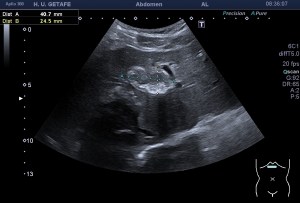

Al llegar al compartimento 6 me encuentro un tendón engrosado de tamaño y aspecto heterogéneo típico de afectación por tendinosis, con líquido en la vaina, te lo señala la imagen con flecha amarilla. Lo recorro y confirmo los hallazgos eje corto y eje largo, hago medidas y compruebo el doppler que marca Neovascularización asociada.

Observa las tres imágenes superiores, son muy ilustrativas, son comparativas de normalidad hallazgos patológicos, el izquierdo claramente patológico y el derecho claramente normal.